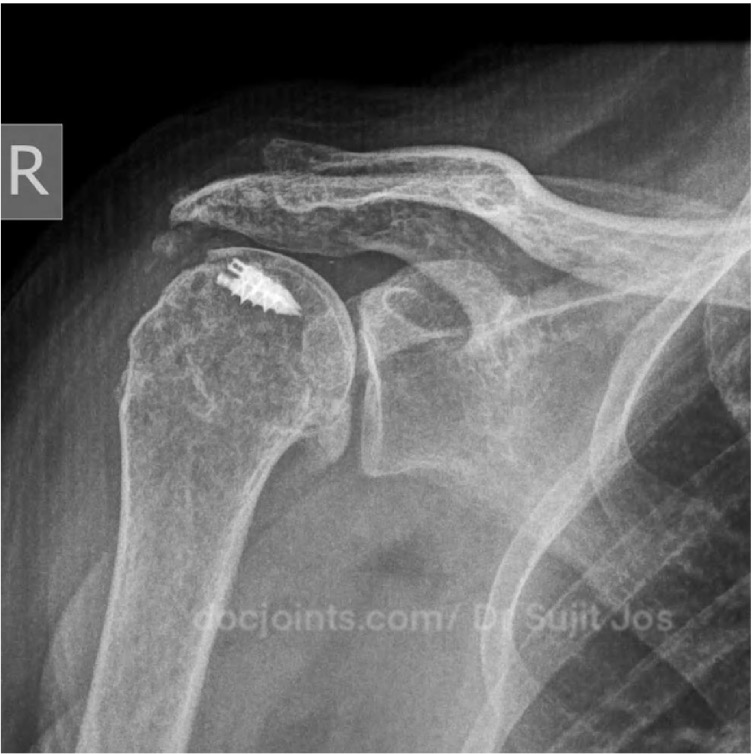

Re Retear of Rotator cuff repair done elsewhere. Failed Rotator Cuff Repair Managed with Reverse Shoulder Arthroplasty

For nearly two years, she had been struggling with persistent shoulder pain. Simple daily activities — combing her hair, dressing, even sleeping — had become difficult. She had already undergone two surgeries for her shoulder at another center, hoping each time that things would finally improve.

The tendon in her shoulder was severely damaged and no longer repairable. Repeating the same type of surgery again would not help her.

At this stage, we discussed the available options with her. Considering her age, the condition of the joint, and her previous surgeries, we recommended a reverse shoulder replacement — a procedure designed to restore function even when the tendons are no longer working.